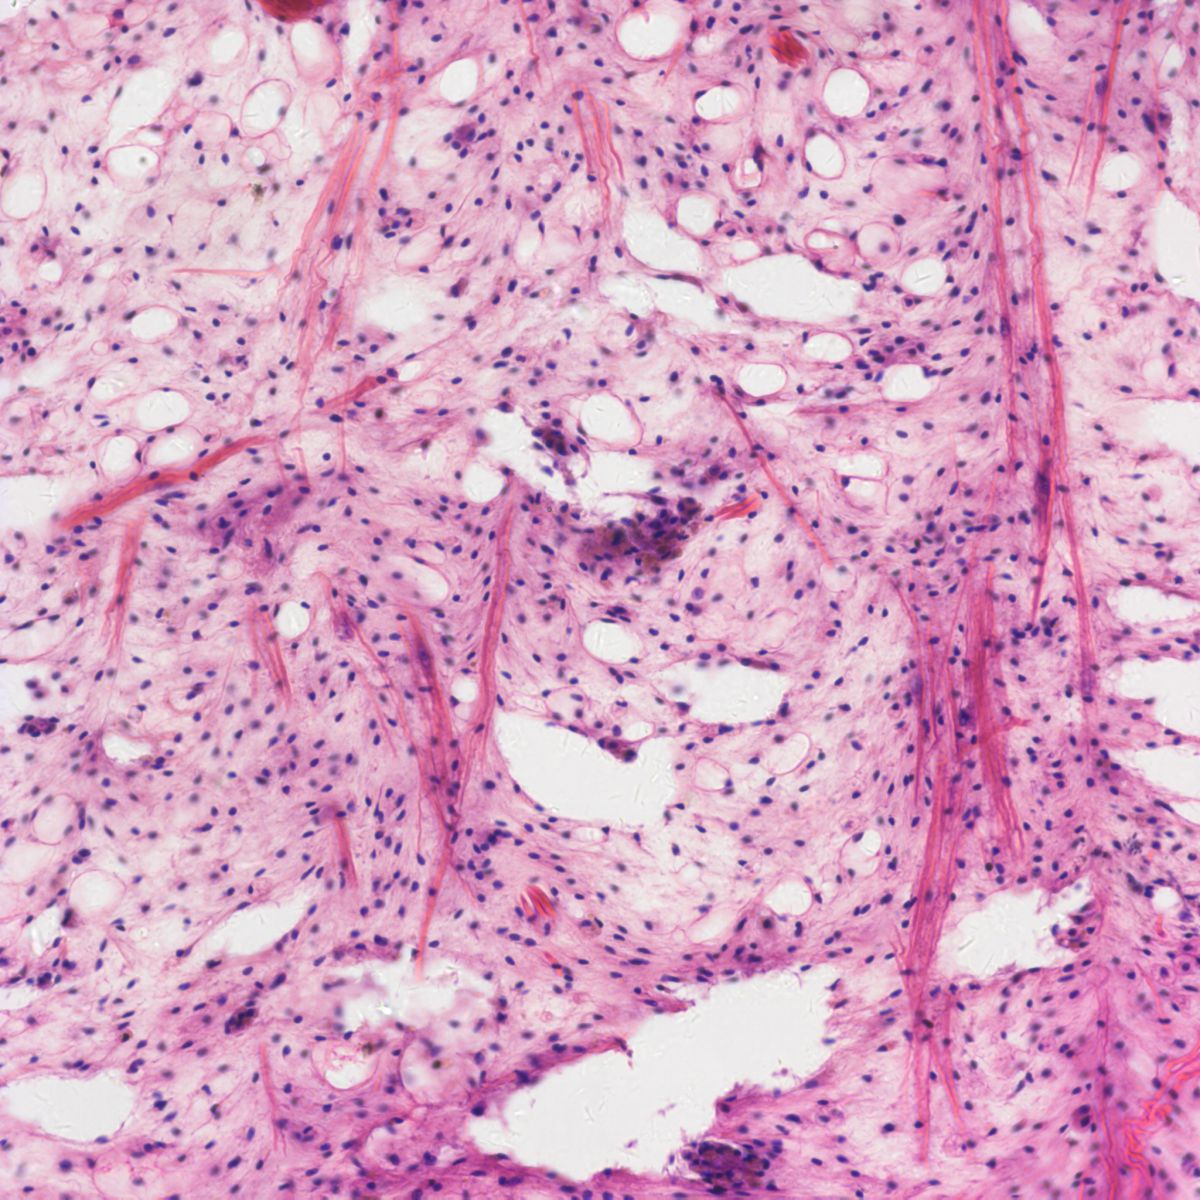

病理圖像分析對數碼成像的藍\紫\紅色提出了很高的要求,400DC在這些區域的完美表現,可以為病理分析判斷提供可靠的依據。

400DC應用圖欣賞